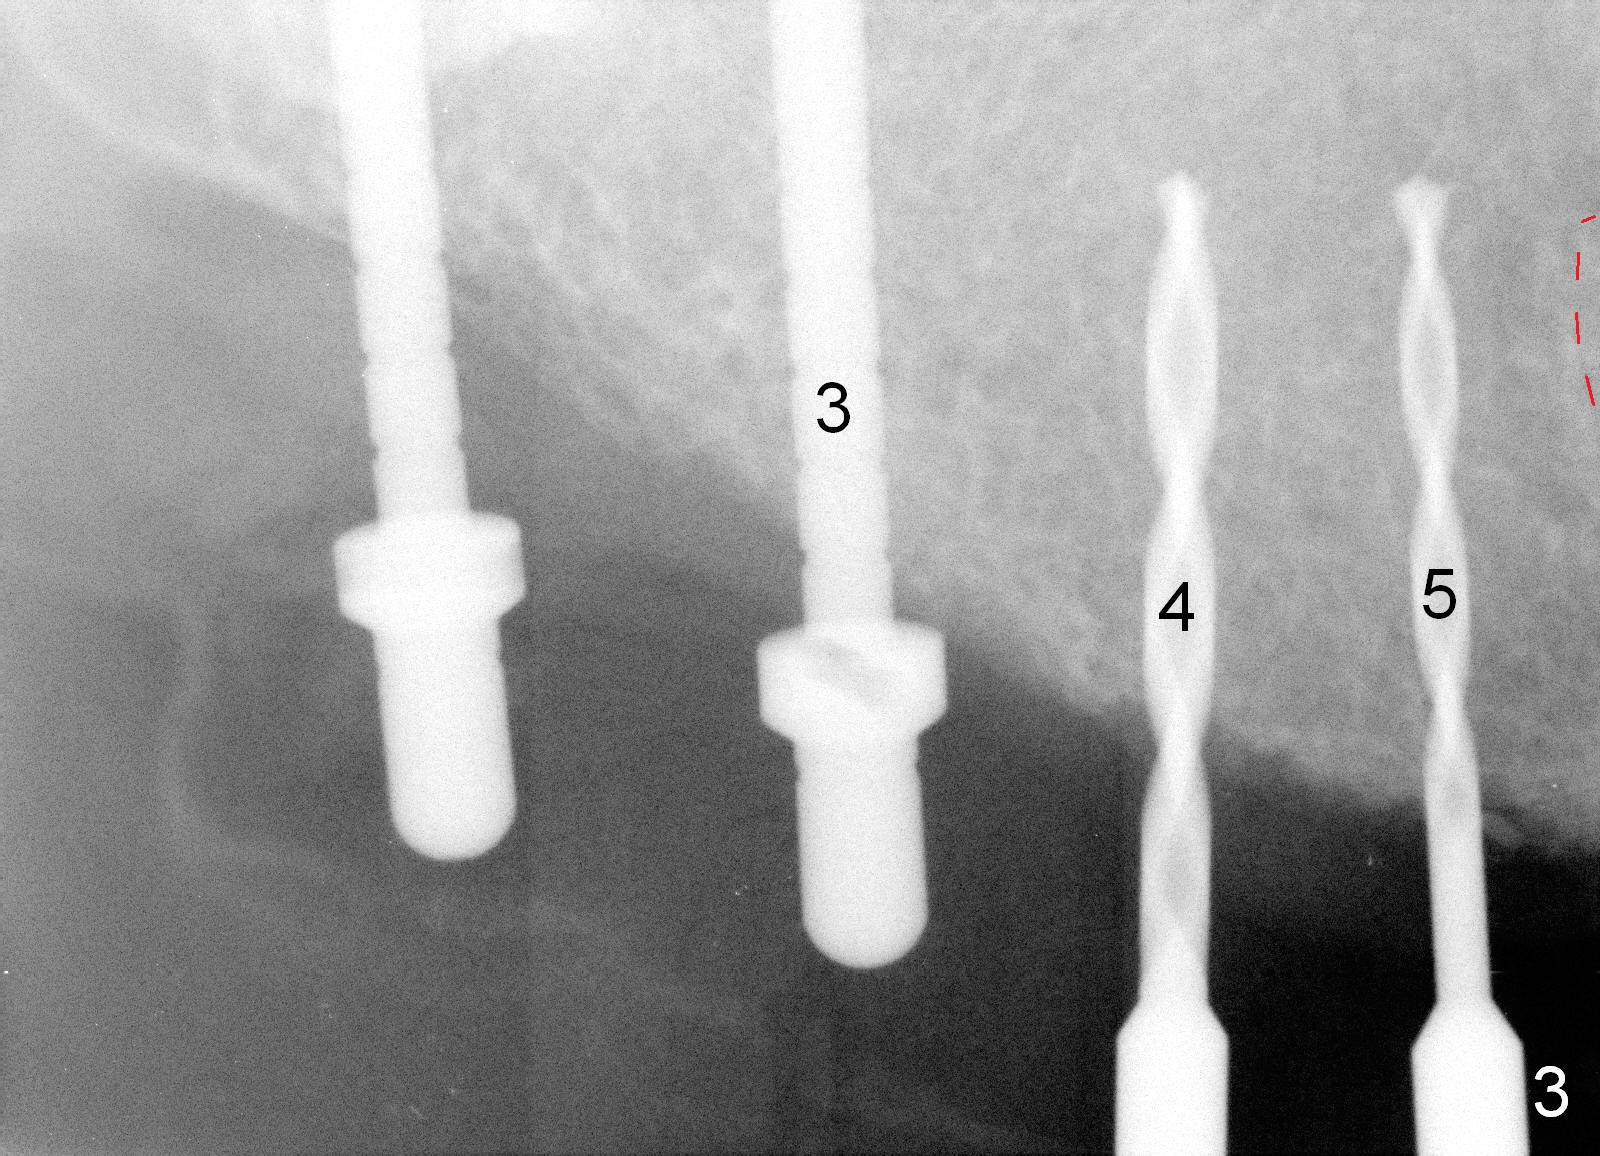

Osteotomy in the upper posteriors starts through a surgical stent for 12 mm. After incision, each osteotomy is examined, adjusted and extended 2 mm shy of intended (Fig.1,2). It appears that the trajectories at #4,5 are off (Fig.2). After re-adjustment, the trajectories are acceptable (Fig.3 (red dashed line; part of the root of the tooth #6)). Four implants are placed basically in accordance with the plan: 5.9x10 mm at #2, 5x14 at 3, and 3x14 mm 1-piece at 4 and 5 (Fig.4,5). Fig.6 shows the narrow ridge at #4 and 5 after implant placement. Although abutments are placed at #2 and 3, an immediate provisional bridge cannot be fabricated because of lack of enough clearance (supraeruption of the opposing dentition).